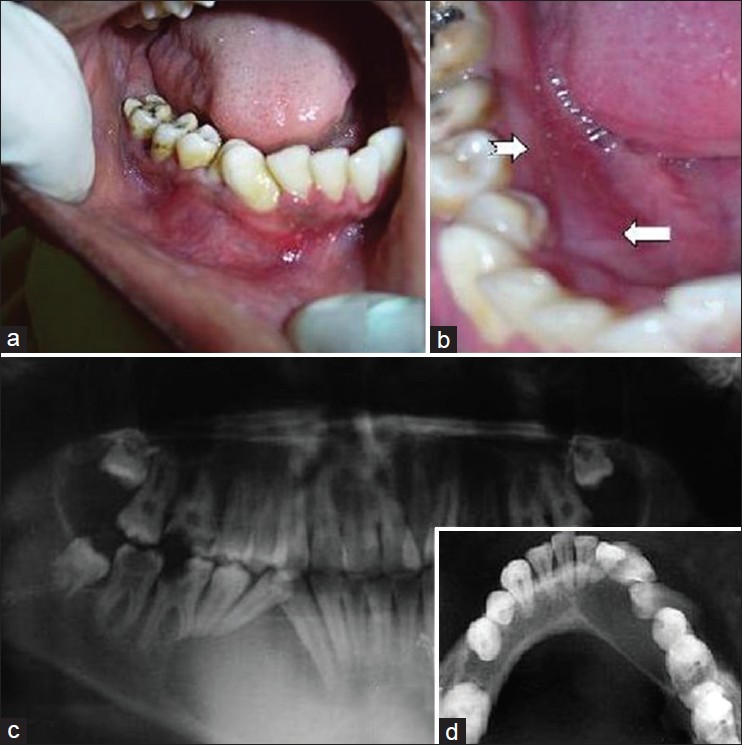

Unilateral gingival fibromatosis

p. 320

Monal Yuwanati, Akash Akinwar

DOI

:10.4103/2278-9626.116001

Increase in size of gingiva is termed as gingival enlargement or gingival overgrowth; characterized by expansion and accumulation of the connective tissue. Enlargement of gingiva can be classified according to etiology, pathogenesis, location, and distribution. Many forms of gingival Hyperplasia are of unknown etiology and termed as idiopathic gingival fibromatosis. Gingival fibromatosis is classified as two types according to its form. The localized nodular form is characterized by the presence of multiple localized enlargements in the gingiva and the other one is most common symmetric form results in uniform enlargement of the gingiva. Our aim in this case report is to present a very interesting case of patient with the unusual clinical forms of unilateral gingival fibromatosis and to discuss the histopathological and clinical features in comparison to similar enlargements.